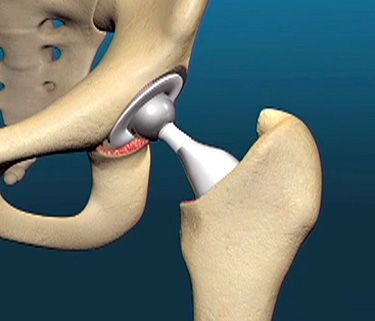

Hip Replacement, also known as Hip Arthroplasty, is a surgical procedure in which a damaged or diseased hip joint is replaced with an artificial implant made of metal, ceramic, or medical-grade plastic. This surgery is commonly recommended for patients suffering from severe hip pain, stiffness, and restricted movement due to conditions such as osteoarthritis, rheumatoid arthritis, avascular necrosis, hip fractures, or long-standing joint damage.

During the procedure, the surgeon removes the damaged portions of the hip joint and replaces them with an artificial socket and ball that restore smooth movement. Hip replacement helps relieve chronic pain, improve mobility, correct joint deformities, and enhance overall quality of life. After surgery, patients undergo physiotherapy and rehabilitation to regain strength, balance, and flexibility. With proper post-operative care, most patients experience long-term pain relief and a significant return to daily activities.